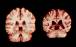

به گزارش سیناپرس، نقش ژنتیک در سه بیماری لنف ادم اولیه، بیماری آنوریسم آئورت قفسه سینه و ناشنوایی مادرزادی، پیش از این شناخته نشده بودند. درک بهتر از عملکرد ژن های دخیل در این اختلالات میتواند راه را برای ایجاد و توسعه درمانهای جدید هموار کند.

در لنف ادم اولیه، دستگاه لنفاوی (غدد و رگ های لنفاوی) به صورت مادرزادی دچار نقص است و نمی توانند مایع لنف را به خوبی انتقال دهد. علایم لنف ادم اولیه، اغلب پس از ۳۵ سالگی بروز می کند.

آنوریسم آئورت قفسه سینه، موجب گشاد شدن و در نهایت پارگی سرخرگ ها می شود. سرخرگ آئورت از سرخرگ های اصلی متصل به قلب است. پاره شدن این سرخرگ باعث خونریزی داخلی می شود و این مسئله، تهدیدی جدی برای ادامه حیات بیمار است.

محققان مجموعه ای از ۲۶۹ بیماری نادر و داده های ۷۷ هزار شرکت کننده را مورد مطالعه قرار دادند. بعداز بررسی ها، پژوهشگران، ۲۶۰ ارتباط بین ژن های مختلف و بیماری های نادر مشاهده کردند که تعداد زیادی از آنها پیش از این شناخته نشده بودند.